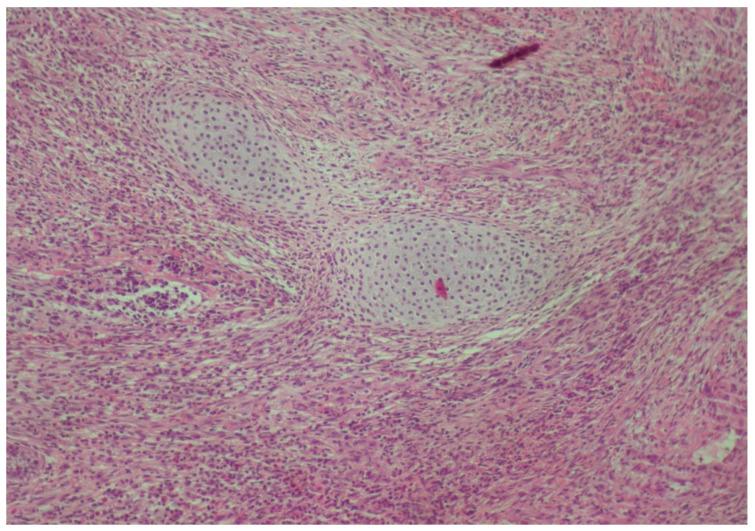

一名6岁男性患者被转诊至希腊塞萨洛尼基亚里士多德大学健康科学学院牙科学院口腔医学/病理学系的研究生诊所,因为他的儿科牙医在常规检查中发现牙齿#75远中处有一个外生性口腔内肿块。首次组织病理学检查显示为牙龈肿瘤,归类为小圆蓝细胞瘤,与釉质瘤样尤因肉瘤(ALES)更为相似,与滑膜肉瘤的相似性较小。第二位病理学家检查了相同的组织标本,并提示极罕见地存在未成熟恶性畸胎瘤。化疗后,切除了畸胎瘤剩余部分及相邻的牙齿#75,组织病理学检查显示为成熟畸胎瘤。